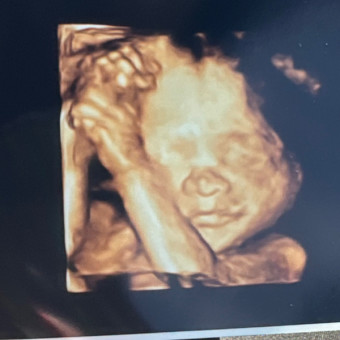

Help us prepare for the arrival of Avaleigh Lynn Babb🩷! We appreciate anything you are able to help us buy!